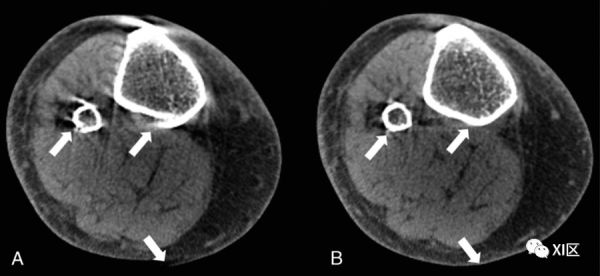

在自动聚焦方法中,通过执行数值优化以估计运动轨迹来实现补偿,该运动轨迹最小化运动引起的图像域失真的某些度量;在肌肉骨骼CBCT中,图像梯度的方差被用作度量。在涉及运动污染的肢体CBCT扫描的专家观察者研究中,自动聚焦校正体积显示出改进的诊断质量(图2)。

图2. WB-CBCT中的自动聚焦运动补偿。A、带有特征伪影图案(条纹和双轮廓)的运动污染扫描(箭头)。B、自动聚焦补偿可显著减少伪影(箭头)。